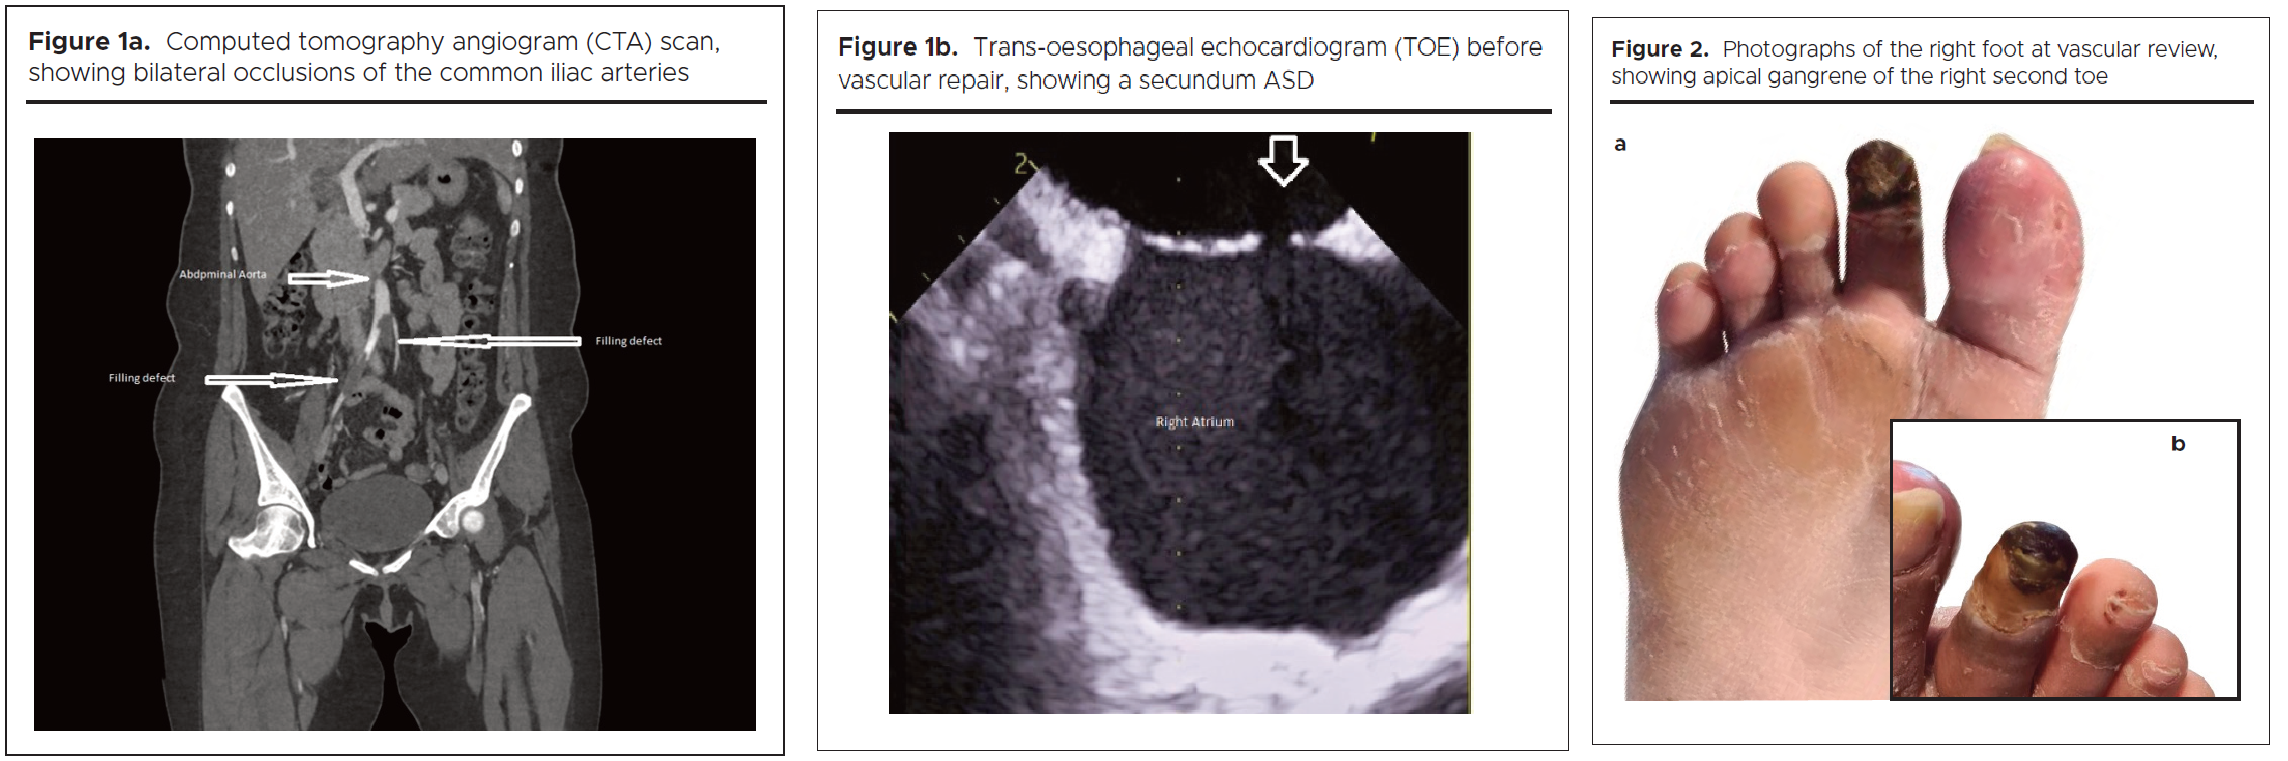

An arterial Duplex ultrasound identified subacute tight stenosis of the distal aorta, with occlusion of the right external iliac artery and right trifurcation. Computed tomography (CT) angiography demonstrated a small filling defect of the distal aortic arch, bilateral occlusions of the common iliac arteries (figure 1a), and occlusion of the right tibio-peroneal trunk.

Extensive thrombophilia screening did not identify any underlying predisposition to thrombosis, and no predisposing medications (such as oral contraceptive pill use) were implicated. A 24-hour cardiac tape demonstrated sinus tachycardia with no arrhythmias. Trans-oesophageal echocardiogram (TOE) revealed an asymptomatic secundum ASD (figure 1b), with left-to-right shunting and no associated risk factors. A diagnosis of paradoxical embolism causing bilateral arterial lower limb ischaemia, particularly affecting the right foot, was made. No viable options for revascularization were identified. She was managed medically with an unfractionated heparin infusion. This was switched to treatment dose subcutaneous dalteparin alongside warfarin until a target international normalised ratio of 2-3 was achieved. Lifelong anticoagulation and ASD closure were recommended, with cardiology follow-up scheduled. The patient was advised to contact the vascular team if she had any concerns relating to changes in her leg.

Clinical course

Six weeks later, while attending for a Monofer infusion for iron-deficiency anaemia, she reported to the medical day unit team that she had noticed some purple discolouration of the toes of her right foot. An urgent vascular review was arranged. Arterial Duplex ultrasound showed multiple occlusions in the lower limb arteries, characterised by monophasic waveforms and limited perfusion. She continued on anticoagulation. The case was discussed at the vascular multidisciplinary team (MDT) meeting, where it was agreed to prioritise closure of the ASD, given the absence of a clear indication for revascularisation at that stage. At her two-week vascular follow-up review, limb-threatening ischaemia was evident, with apical gangrene of the right second toe and hallux embolic patches (figures 2a and b). Toe pressures were absent bilaterally. The right ankle-brachial pressure index (ABPI) was too faint to assess, while the left measured 0.5, consistent with moderate arterial insufficiency.